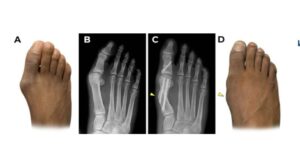

What is a Pseudo Bunion.? This results when the orthopedic surgeon decides to do their type of minimal incision surgery. They use these large screws. This results in a bony deformity in the back. Which then grows into a bony growth. Now you will have 2 bunions for the price of 1. Stay away from these doctors that perform these types of procedures. These procedures are performed in the hospital and under general anesthesia.

At the Comprehensive Foot and Ankle Institute, we perform corrective bunion procedure with the True Minimal Incision type of surgery. This involves performing a corrective surgery without the use of any internal hardware such as screws and plates. With our regenerative medicine and minimal incision type surgery we can perform these procedures in the office.